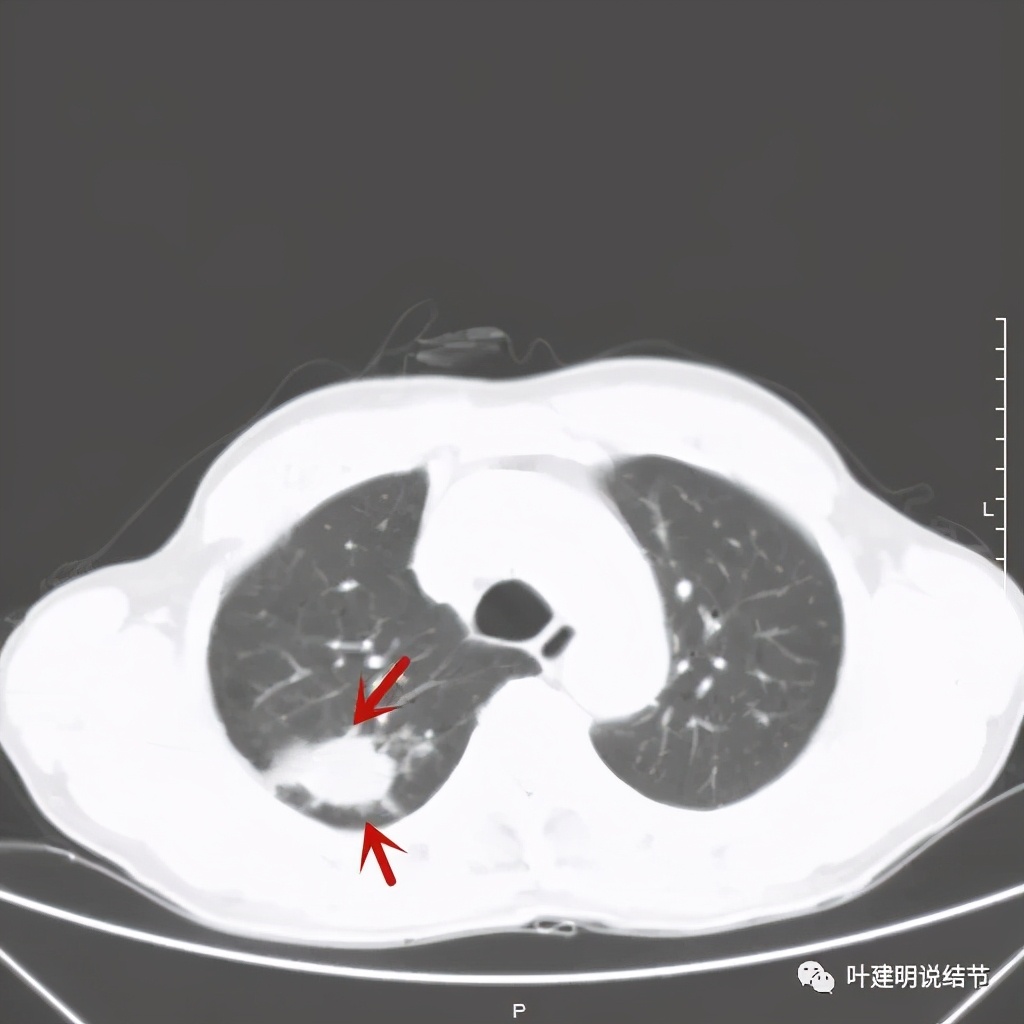

红色示病灶,绿色示病灶旁边有磨玻璃成分,但较为模糊;蓝色箭头示病灶与胸膜间有牵拉,但力度不太够。

总体上感觉,病灶比较大,不规则,不是圆形或圆形生长,周围有模糊磨玻璃影(考虑炎性渗出性?),虽有胸膜牵拉,但力度不够;增强有显著强化。病灶明显却无明显临床症状,普通感染是不像的,要么是结核,要么是肺癌。但肺癌的话,在2年前没有,2年内长到这么大,恶性程度应该很高,但其纵隔淋巴结却没有明显肿大。而且病灶的边缘部分过于光滑,没有见到肿瘤的细毛刺,膨胀性也不够。整体看病灶有点像“腰子”形,弯弯曲曲的。所以我的感觉更倾向结核性。查了肿瘤筛查指标如下: